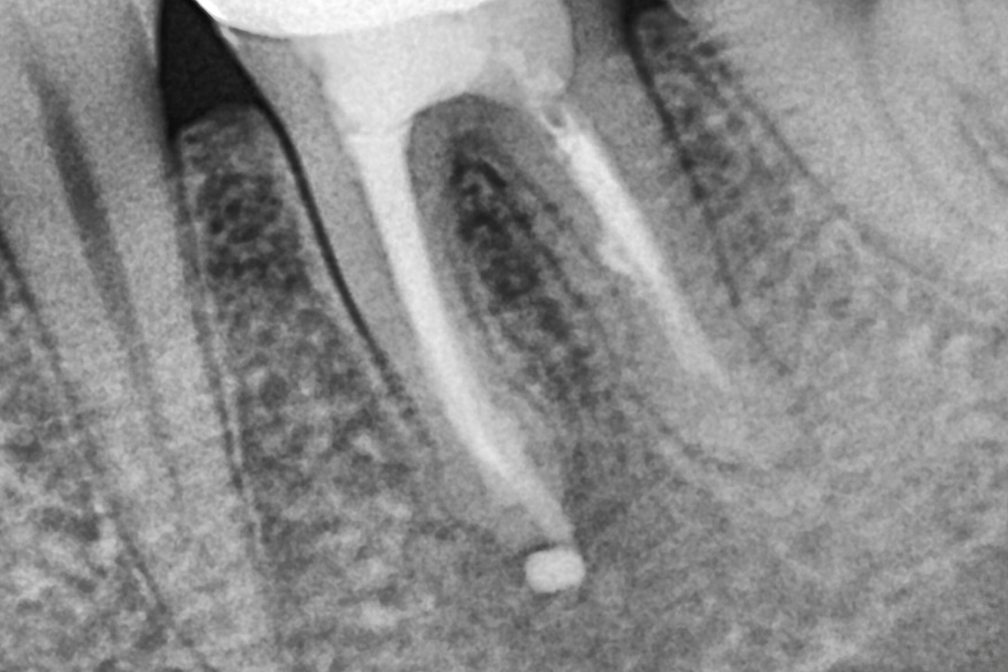

Before 2025년 6월 7일